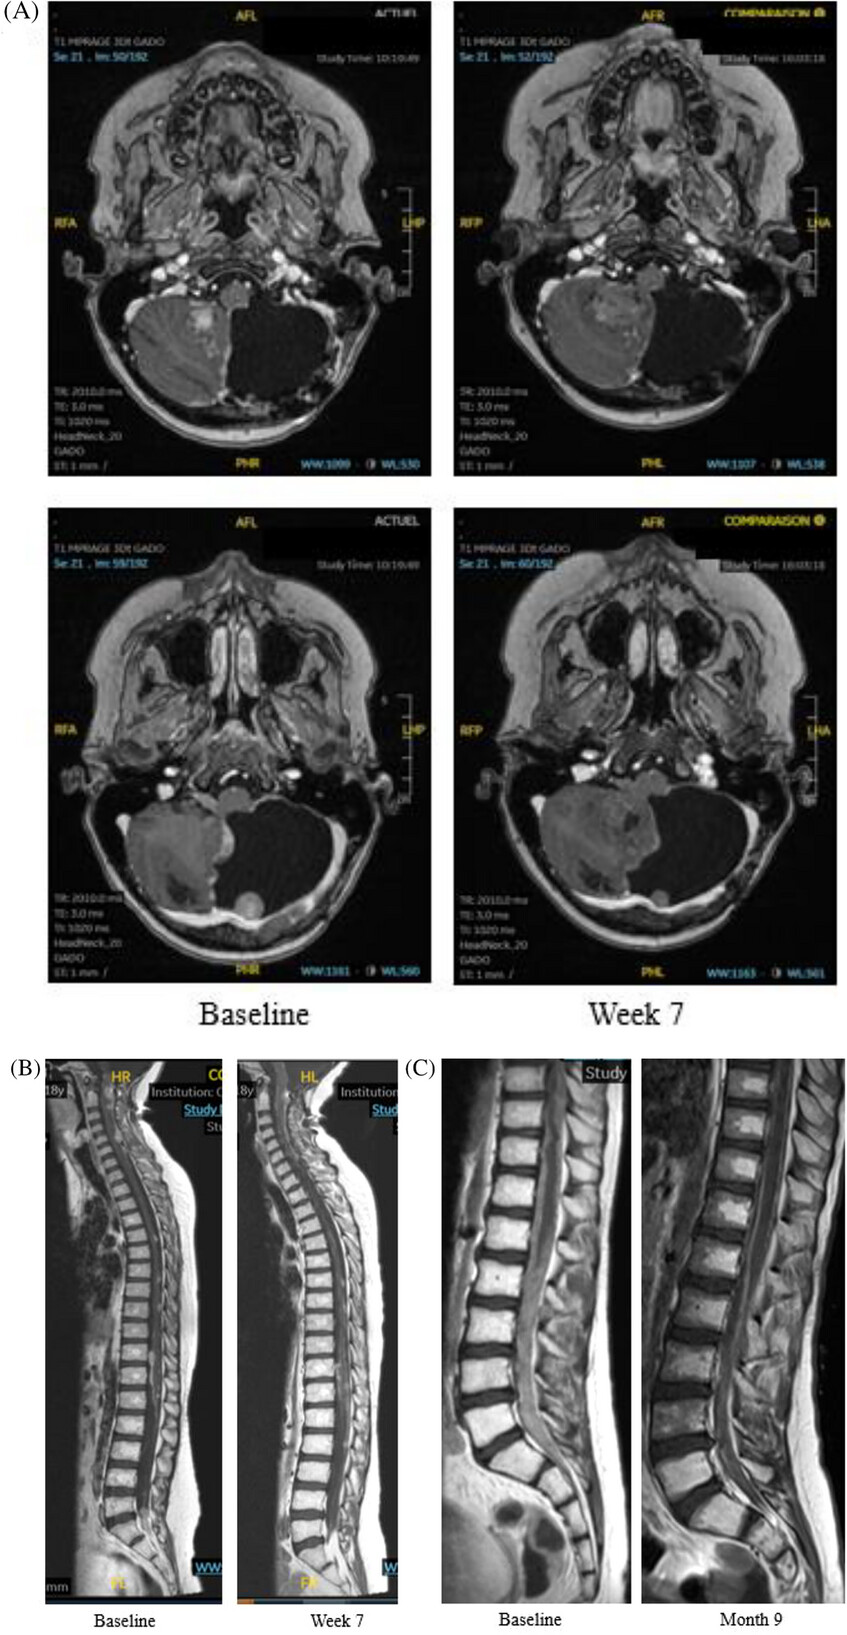

Interestingly, 3 patients with medulloblastoma experienced partial response; one patient with atypical teratoid rhabdoid tumor (ATRT) displays an ongoing stable disease (12 months); two patients with medulloblastoma had progressive disease. Grade 3–4 toxicities were observed in two patients (thrombocytopenia, anemia, diarrhea, fatigue). The axitinib–etoposide combination shows signals of efficacy in heavily pretreated patients with relapsed/refractory brain tumors. These results were based on real-world observation and will need formal evaluation in a phase I/II trial.The full text of the article is freely available here